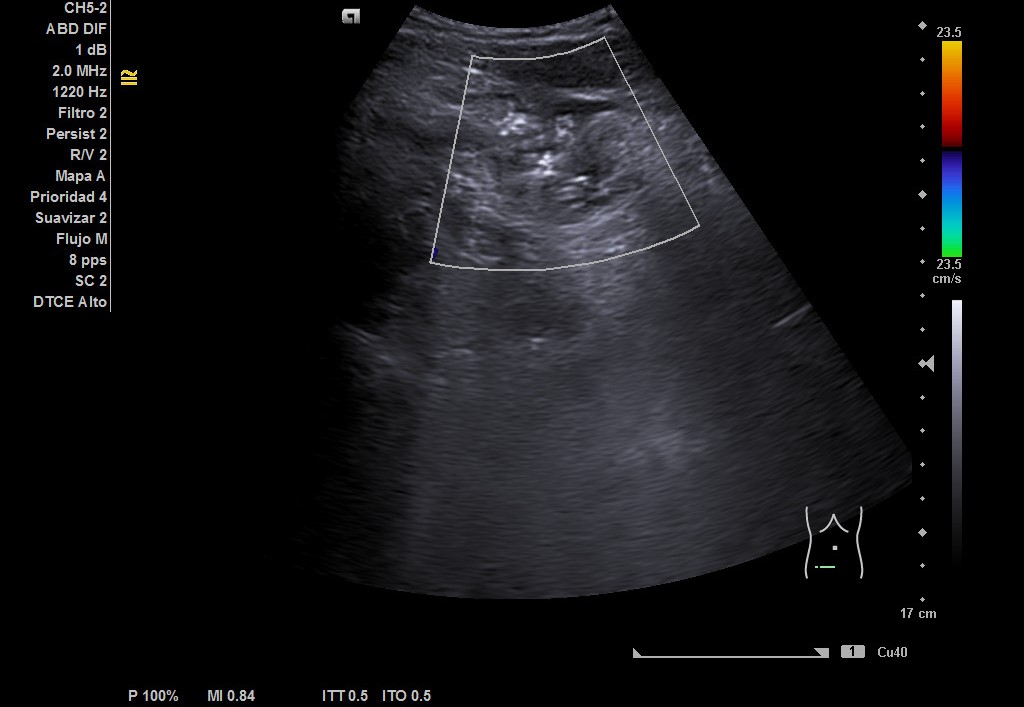

Hallazgos ecográficos

Hígado de tamaño, forma y ecoestructura conservadas, con parénquima homogéneo. Vena porta de calibre conservado.  Ausencia de signos de dilatación de la vía intra o extrahepática. Vesícula biliar de paredes finas, sin contenido ecogénico en su interior. Páncreas de características normales. Riñones de tamaño y localización conservada, sin hidronefrosis. En FID imagen heterogénea delimitada, de 50x30 mm, con posible edema de pared y focos ecogénicos en su interior.